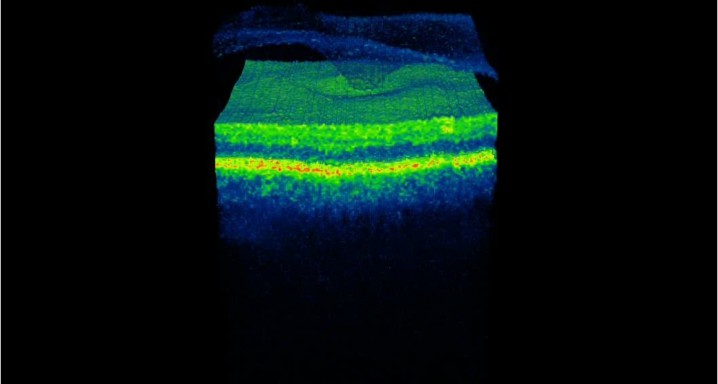

Assessment of Anatomical and Functional Outcomes in Patients Treated with Ocriplasmin for Vitreomacular Traction/Symptomatic Vitreomacular adhesion (VMT/sVMA). Clinical trial M-13-056.

Evaluará los resultados anatómicos y funcionales en los pacientes tratados con una sola inyección intravítrea de JETREA (Ocriplasmina), durante un periodo de 6 meses. Ensayo clínico en fase IV.

Inyecciones intravítreasSíndrome de tracción vitreomacular